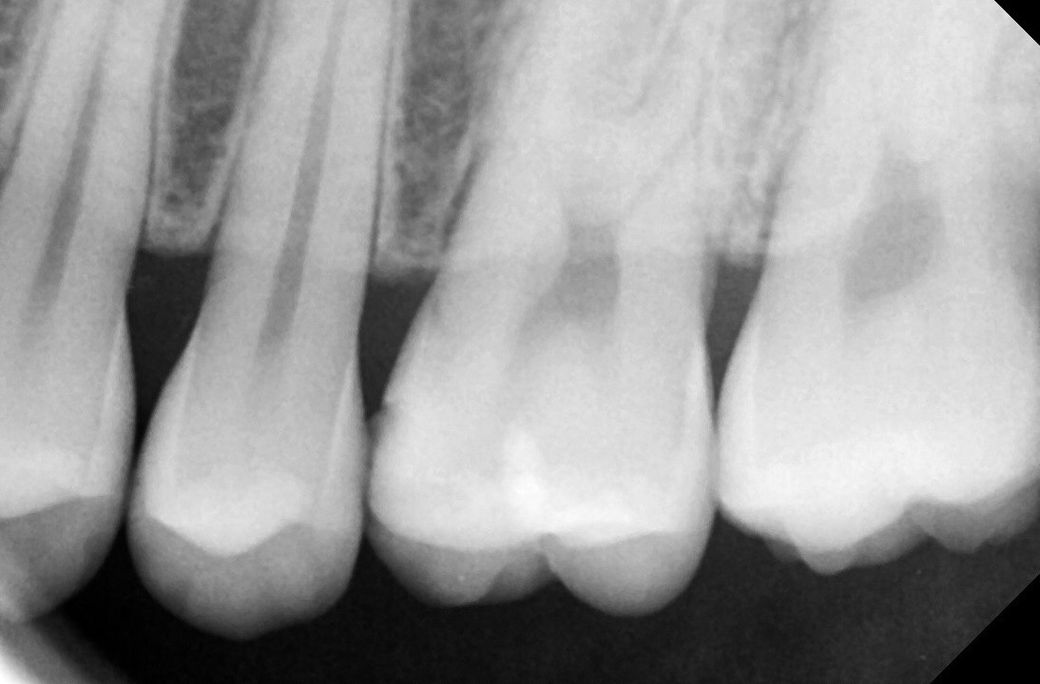

1치과는 충치가 있는 것 같다 양 옆 색상 차이가 있다 눈으로 확인 되는 정도라면 치료 해야 할 시기이다

위치 왼쪽 위 2번째 어금니 치료 한 부위 2차 충치

왼쪽 위 4번째와 3번째 사이 인접면 충치

• 2번 째 사진

사진에 보이는 정도면 충치가 안쪽에 많이 진행됫을 가능성이 있습니다. 저라면 인레이로 치료를 할것같습니다.

육안으로 보였을 경우 인절면에 충치가 있는 것으로 보입니다. 하지만 방사선상에는 크게 보이진 않습니다. 눈으로 보이는 충치가 있기 때문에 인접면 충치는 치료를 하는 것이 좋을 것으로 생각됩니다.

레진보다는 인레이를 하는 것이 일반적이며 레진은 술자를 잘 선택하셔야 합니다. 치료는 필요해보입니다.